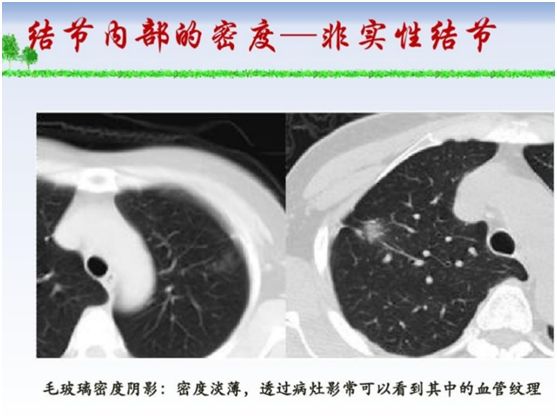

其实“肺部结节”不是疾病的学名,是指在拍片时看到的比较小的阴影,有良性、恶性之分,根据结节的密度不同,可以分为磨玻璃结节、部分实性磨玻璃结节和实性结节,这三类结节中恶性病变所占比例分别是18%、63%和7%。

医生会根据结节的生长方式、边缘形态、内部密度高低、周围血管结构来综合分析判断结节的性质,但是早期肺癌的诊断仍然是比较困难的。定期复查肺部发现结节的生长速度、内部结构、边缘改变等都是判断肺部结节良恶性的重要依据。